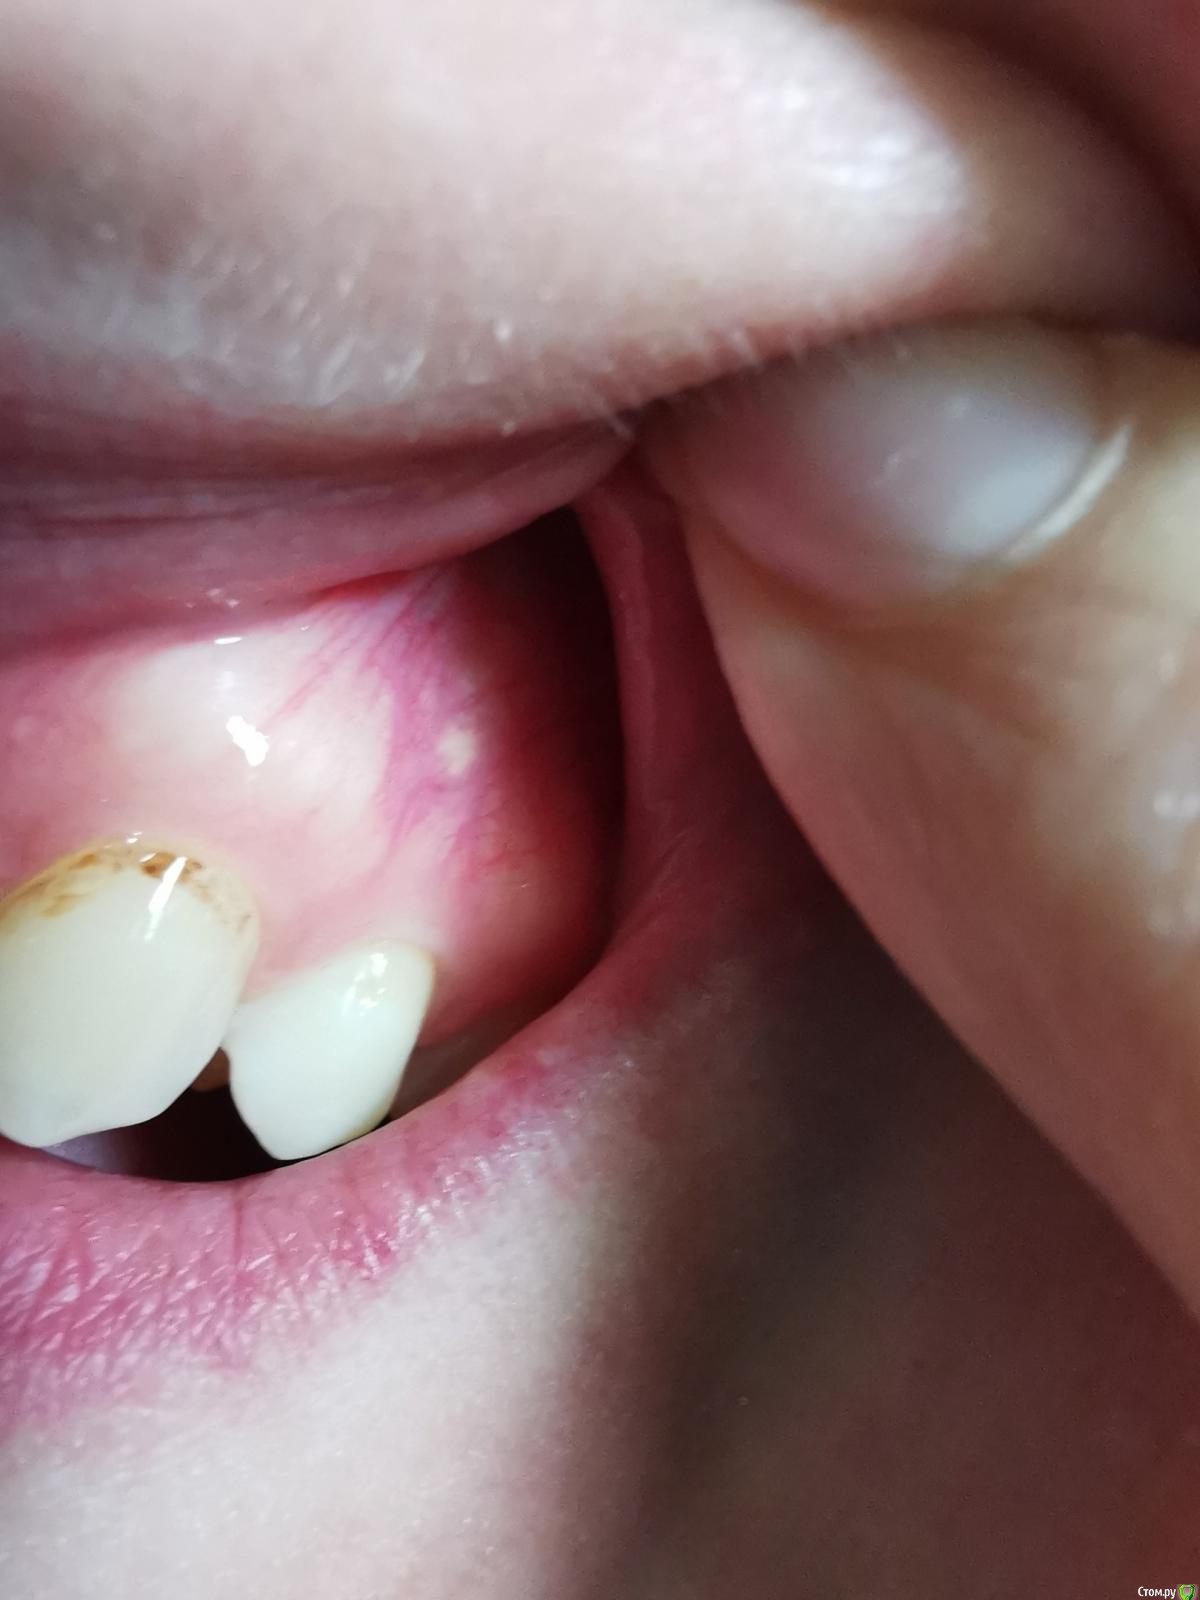

В мае 2020 заметила белое образование на слизистой альвеолярного отростка/десны. Никак не беспокоит, гладкое, не болит, не выпуклое, без изъязвлений, под слизистой не подвижно(не отдельное). Со стороны выглядит как кусочек жировой ткани. С мая месяца увеличилось немного (либо я себе напридумывала...)

Фотографии прикрепляю, не знаю на сколько это будет информативно, но может подскажете чем может являться данное образование?